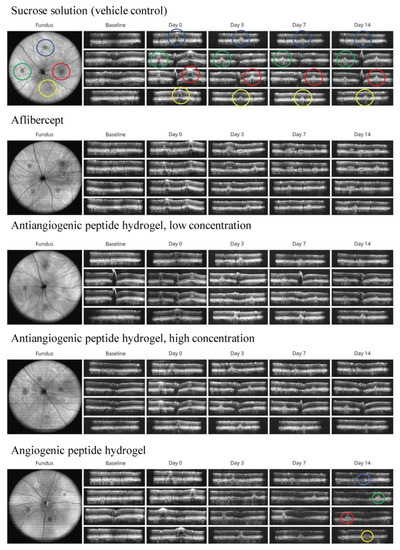

3.2. Qualitative Analysis of CNV Lesions